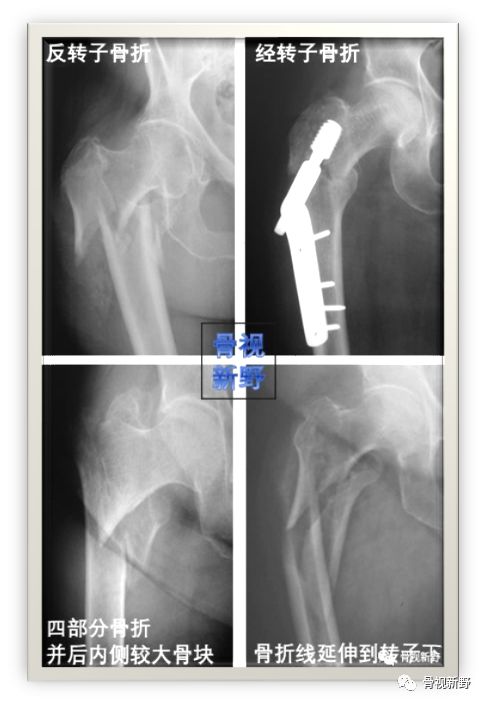

常见四种明显不稳定类型(下图)

对这几种明显不稳定骨折,选择髓内钉较滑动髋螺钉有诸多优势:中心性固定比DHS等钉板系统的偏心性固定力臂较短;髓内钉还能有效抵抗通过股骨矩的较高应力,而这部分应力在不稳定骨折者完全由内植物承受;

髓内钉还能防止股骨干内移,这是经转子、反转子骨折常见的并发症。